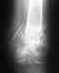

Система Fixion Evropa-Med

Здравствуйте! В феврале 2007 г. получила перелом обеих костей голени в нижней трети (горнолыжная травма),выполнен интрамедуллярный остеосинтез,установлена система Fixion Evropa-Med(в Андорре).Вопрос:нужно ли удалять и когда?где? Мне 54 года. Проживаю в Москве.